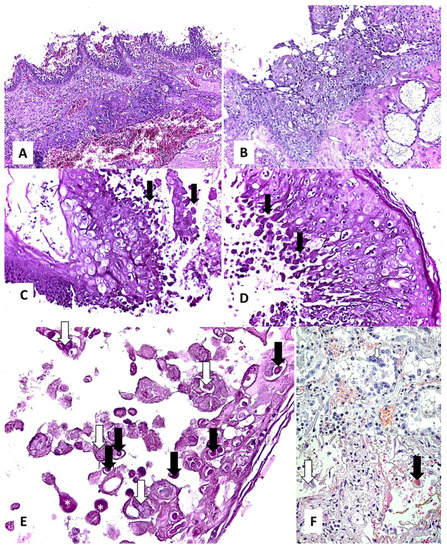

| Squamous metaplasia | 28% (n = 7/25) (Figure 1E,F) | 41.6% (n = 5/12) (Figure 2B–D) | - |

| Basal membrane thickening | 68% (n = 17/25) (Figure 1G,H) | 33.3% (n = 4/12) | - |

| Stromal fibrosis | 36% (n = 9/25) (Figure 1I,J) | - | - |

| Viral cytopathic effect | - | 8.3% (n = 1/12) (Figure 2C–E) | - |

| Microbial biofilms | 40% (n = 10/25) (Figure 1I,J) | - | - |